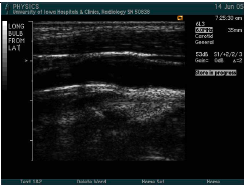

what windows are used when imaging the carotid?

Anterior

Lateral

Posterior

Begin with transverse imaging to determine vessel orientation and presence of plaque.

Continue with longitudinal images.